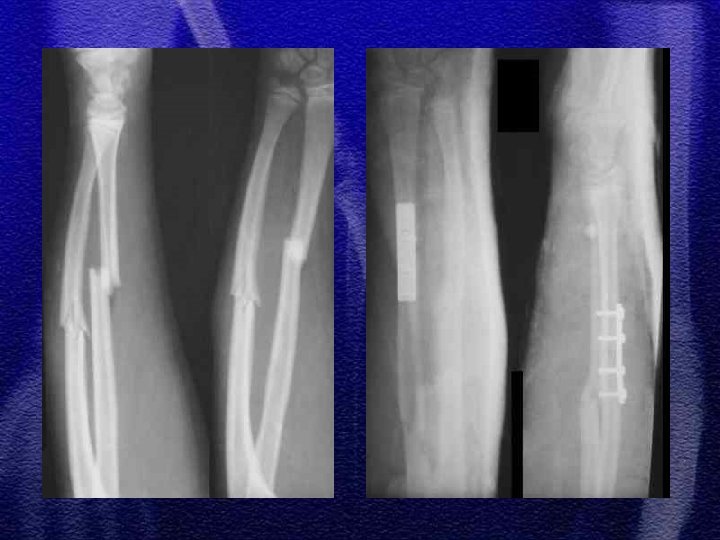

§ Specyficzne - to złamanie typu „zielonej gałązki”, przy złamaniach tego typu okostna nie jest uszkodzona całkowicie, dotyczy to również warstwy korowej § Przy repozycji należy złamać pozostałą warstwę korową, ponieważ zapobiega to wtórnemu przemieszczeniu

§ U dzieci starszych podobnie jak u dorosłych przydatny jest podział dotyczący lokalizacji złamania - określający 3 strefy złamania § W wieku rozwojowym rzadko występuje złamanie typu Galeazzi odmiana dziecięca to złamanie dalszej przynasady kości promieniowej ze złuszczeniem dalszej nasady kości łokciowej

§ Najczęściej repozycja zamknięta § Konieczne kontrole rtg. w 3, 7, 14 dobie z uwagi na możliwość wtórnego przemieszczenia § Leczenie operacyjne - płytki, drut Kirschnera

§ Wyznaczenie jednoznacznego kryterium do zaakceptowania zrostu nieprawidłowego we wstępnej fazie leczenia jest trudne § Przemieszczenie do boku nawet o szerokość trzonu można zaakceptować § Przemieszczenia kątowego >20° nie można akceptować § Przemieszczenia rotacyjne nie podlegają korekcji § Zasadnicze znaczenie ma wiek dziecka